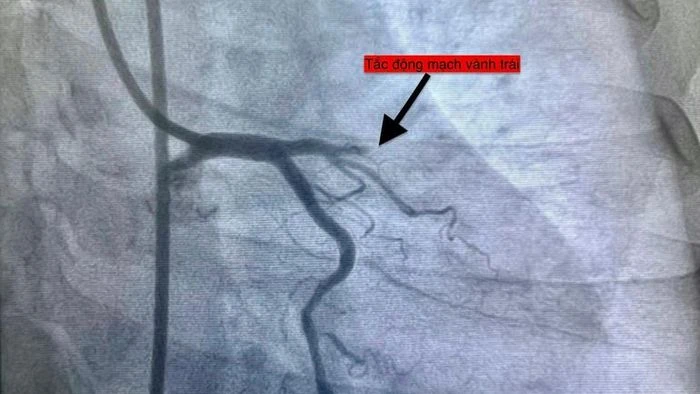

Hình ảnh chụp các ca bệnh nhồi máu cơ tim.